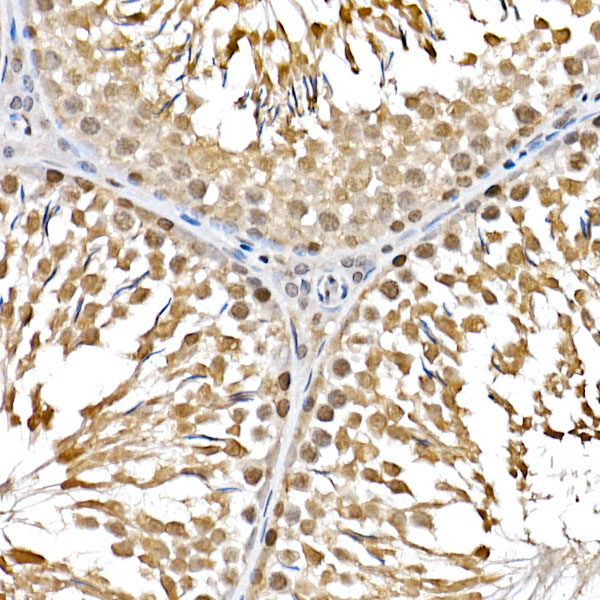

Mammalian target of rapamycin (mTOR) is an atypical serine/threonine kinase that can integrate a variety of extracellular signal stimuli. It is involved in multiple signaling pathways in the body, affecting transcription and protein synthesis. Studies of mTOR found that it has an important connection with processes such as apoptosis, autophagy, and cell growth. For example: 1) mTOR signaling pathway can affect gene transcription and protein synthesis, which plays an important role in cell growth and proliferation. 2) mTOR stability can affect the expression of cytokines in T cells, which is involved in immune suppression. 3) mTOR signaling pathway can affect cell proliferation and protein synthesis, making it a new target for anti-tumor therapy. 4) In addition, mTOR signaling pathway also plays an important regulatory role in diseases such as motor metabolism. mTOR is present in two different complexes, the first being mTOR complex 1 (mTORC1), which consists of mTOR, Raptor, GβL and DEPTOR and is inhibited by rapamycin. The second complex, mTOR complex 2 (mTORC2), consists of mTOR, Rictor, GβL, Sin1, PRR5/Protor-1 and DEPTOR. The function of these two complexes is also different: mTORC1 is responsible for amino acids, oxygen, energy levels, and growth factors, mainly promoting protein synthesis, lipogenesis, energy metabolism, inhibition of autophagy, and lysosome formation. And mTORC2 plays an important role in areas such as muscle Actin cytoskeleton, cell survival, and metabolism.